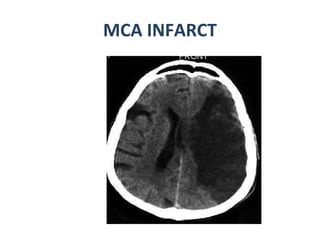

CT- Acute infarct Low density basal ganglia Sulcal effacement Wedge shaphed parenchymal hypo density area that involves both grey and white matter  Increasing mass effect Hemorrhagic transformation  may occur -15 to 45%  (  basal ganglia and cortex common site ) in 24 to 48 hours

MCA INFARCT

CT- Acute infarctLow density basal ganglia Sulcal effacement Wedge shaphed parenchymal hypo density area that involves both grey and white matter Increasing mass effect Hemorrhagic transformation may occur -15 to 45% ( basal ganglia and cortex common site ) in 24 to 48 hours